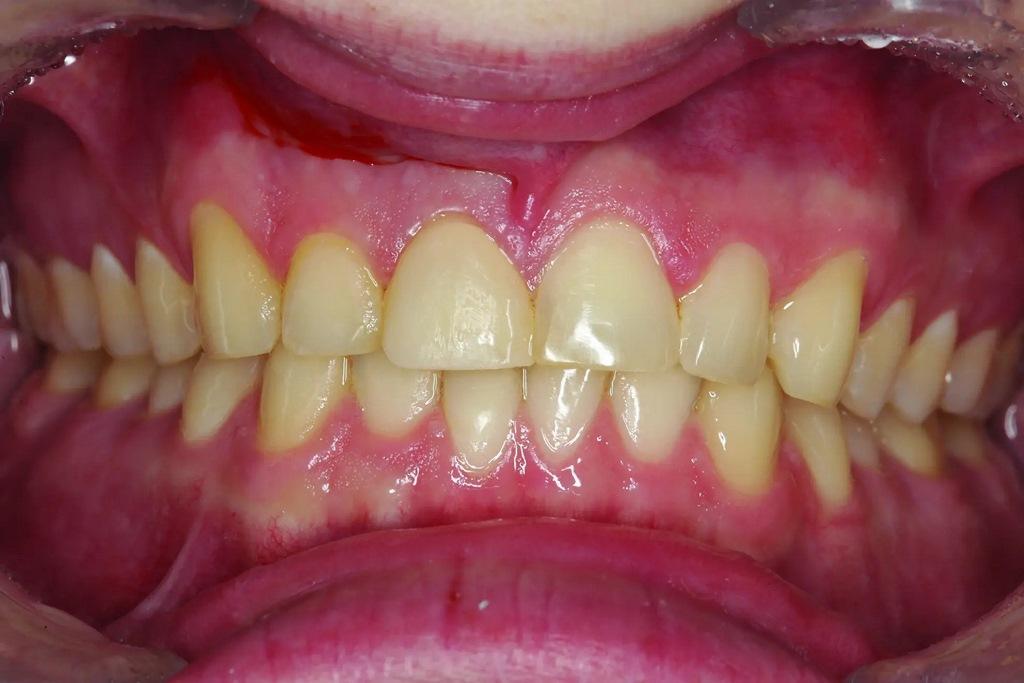

А как насчет выравнивания зубов-антагонистов? На режущих краях зубов 31 и 41 (фото 2) наблюдался чрезмерный износ. Со стороны резцов был виден значительный износ всех краев нижней челюсти из-за окклюзионного заболевания, которое часто наблюдается, но не лечится (фото 3). Также зуб 41 располагался на лицевой стороне таким образом, что при выступающей экскурсии он преждевременно соприкасался с небной поверхностью зуба 11, создавая дополнительную нагрузку как на небную поверхность, так и на резцовый край зуба 11, прежде чем соединиться с остальной частью переднего сегмента верхней челюсти. Это демонстрирует, что решение этих проблем реставрационными методами включает в себя нечто большее, чем просто исправление сколов композитной реставрации.

Фото 3: Резцовый вид показывает, что зуб 41 был наиболее расположенным к лицу резцом нижней челюсти в форме дуги.